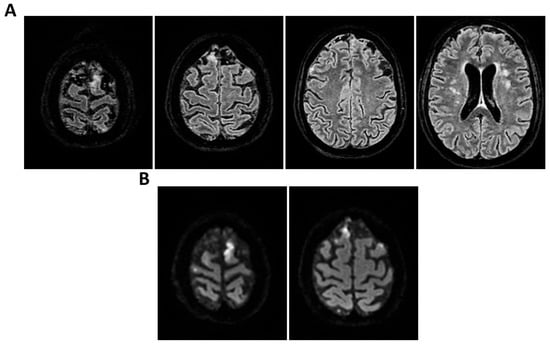

Figure 9.

MRI of patient 4 group 2. A 35-year-old HIV-positive man, diagnosed in 2018 with pneumocystosis (PCP) and non-compliant with Highly Active AntiRetroviral Therapy (Biktarvy), presented with bilateral otalgia, progressive hearing loss, left-sided hemiparesis, and impaired coordination. He was hospitalized and reinitiated Biktarvy and PCP prophylaxis with Bactrim. He received broad-spectrum antibiotics for bilateral otomastoiditis and ganciclovir for CMV viremia. Brain MRI revealed findings consistent with progressive multifocal leukoencephalopathy (PML). After discharge, worsening left hemiparesis and new-onset dysarthria led to readmission. A follow-up CT showed progression of subcortical white matter lesions. Lumbar puncture, urine, and plasma were all positive for JC virus. The patient was transferred to the ICU for further management. On day 2, TCCD showed PI of 1.50 on the right and 1.07 on the left, indicating mild asymmetry but no definitive signs of intracranial hypertension. (A) MRI exam shows large areas of altered signal intensity, without significant mass effect, hyperintense in 3D axial FLAIR sequence, (B) with peripherical diffusion restriction in axial DWI sequence, (C) without contrast enhancement in 3D axial T1 FSPGR, involving both cortical and deep regions of the frontal, temporal and parietal regions bilaterally, as well as right insular and thalamic regions. Additionally, the brainstem with left-sided predominance and the right middle cerebellar peduncle are involved. These alterations are consistent with PML. (D) MRI perfusion study documents minimal increase in CBF in the more cranial regions on the right. Blue circles indicate the ROI used for quantitative CBF analysis.

Figure 10.

MRI of patient 5 group 2. A 67-year-old woman with schizophrenia presented to the ER with lethargy and vomiting, following 10 days of fever and dry cough treated ineffectively with Medrol and Cefditoren. Brain CT showed a left temporoparietal hypodensity (sequela) and supratentorial ventricular dilation without midline shift. The lumbar puncture was positive for Listeria monocytogenes (FilmArray). Due to neurological deterioration (GCS 7), she was transferred to the ICU. On day 2, TCCD showed PI values of 1.65 (right) and 1.89 (left), indicating increased cerebral vascular resistance without clear signs of intracranial hypertension. (A) 3D axial FLAIR shows marked and diffuse atrophy of the brain tissue, more pronounced in the left hemisphere where some areas of enlargement of the cerebrospinal fluid spaces are observed, more prominent in the parietal region, and diffuse dilation of the supraventricular system, particularly in the occipital horns. (B) Perfusion study reveals minimal asymmetry in cerebral perfusion values sampled at the level of the semioval centers. Blue circles indicate the ROI used for quantitative CBF analysis.

3.2. Group 2: TCCD and Perfusion MRI with ASL

The remaining two patients in this group experienced poor outcomes. One was diagnosed with progressive multifocal leukoencephalopathy (PML) due to JC virus and presented with a right-dominant perfusion asymmetry and elevated right-sided PI (1.50). MRI revealed extensive subcortical and infratentorial lesions, including the brainstem (Table 3 and Figure 9).

The second patient, affected by L. monocytogenes meningoencephalitis, showed bilateral elevation of PI (1.65 and 1.89) and significant CBF asymmetry (right CBF: 105 mL/100 g; left CBF: 91 mL/100 g) (Table 3 and Figure 10).

Both patients died by day 28. Notably, these two cases demonstrated a mismatch between regional perfusion and vascular impedance, consistent with cerebrovascular dysregulation and loss of autoregulation.